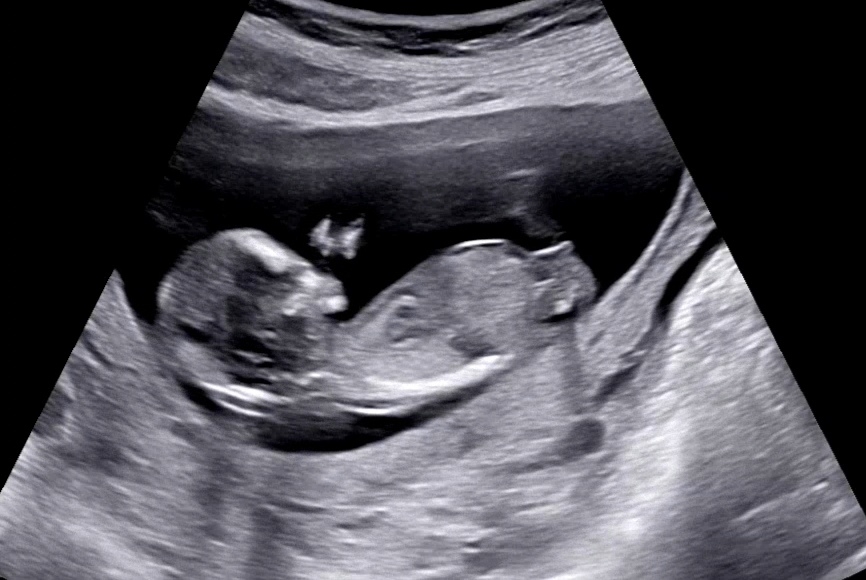

현재 각도는 딸, 시간지나고 더 봐야할서같아요.

각도법 문의드려요🥰

챗지피티는 아들, 딸 다 말하네요 ㅎㅎ

아들 한표 드려요~! 끝이 올라가 있는게 애매하네요ㅎㅎ

저도 딸!

저도 딸이요!